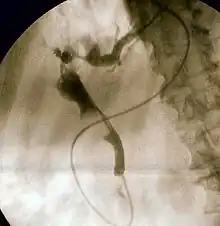

![]() Duodenoscopía que muestra la salida de pus de la ampolla de Vater, un hallazgo clínico de Colangitis. | ||